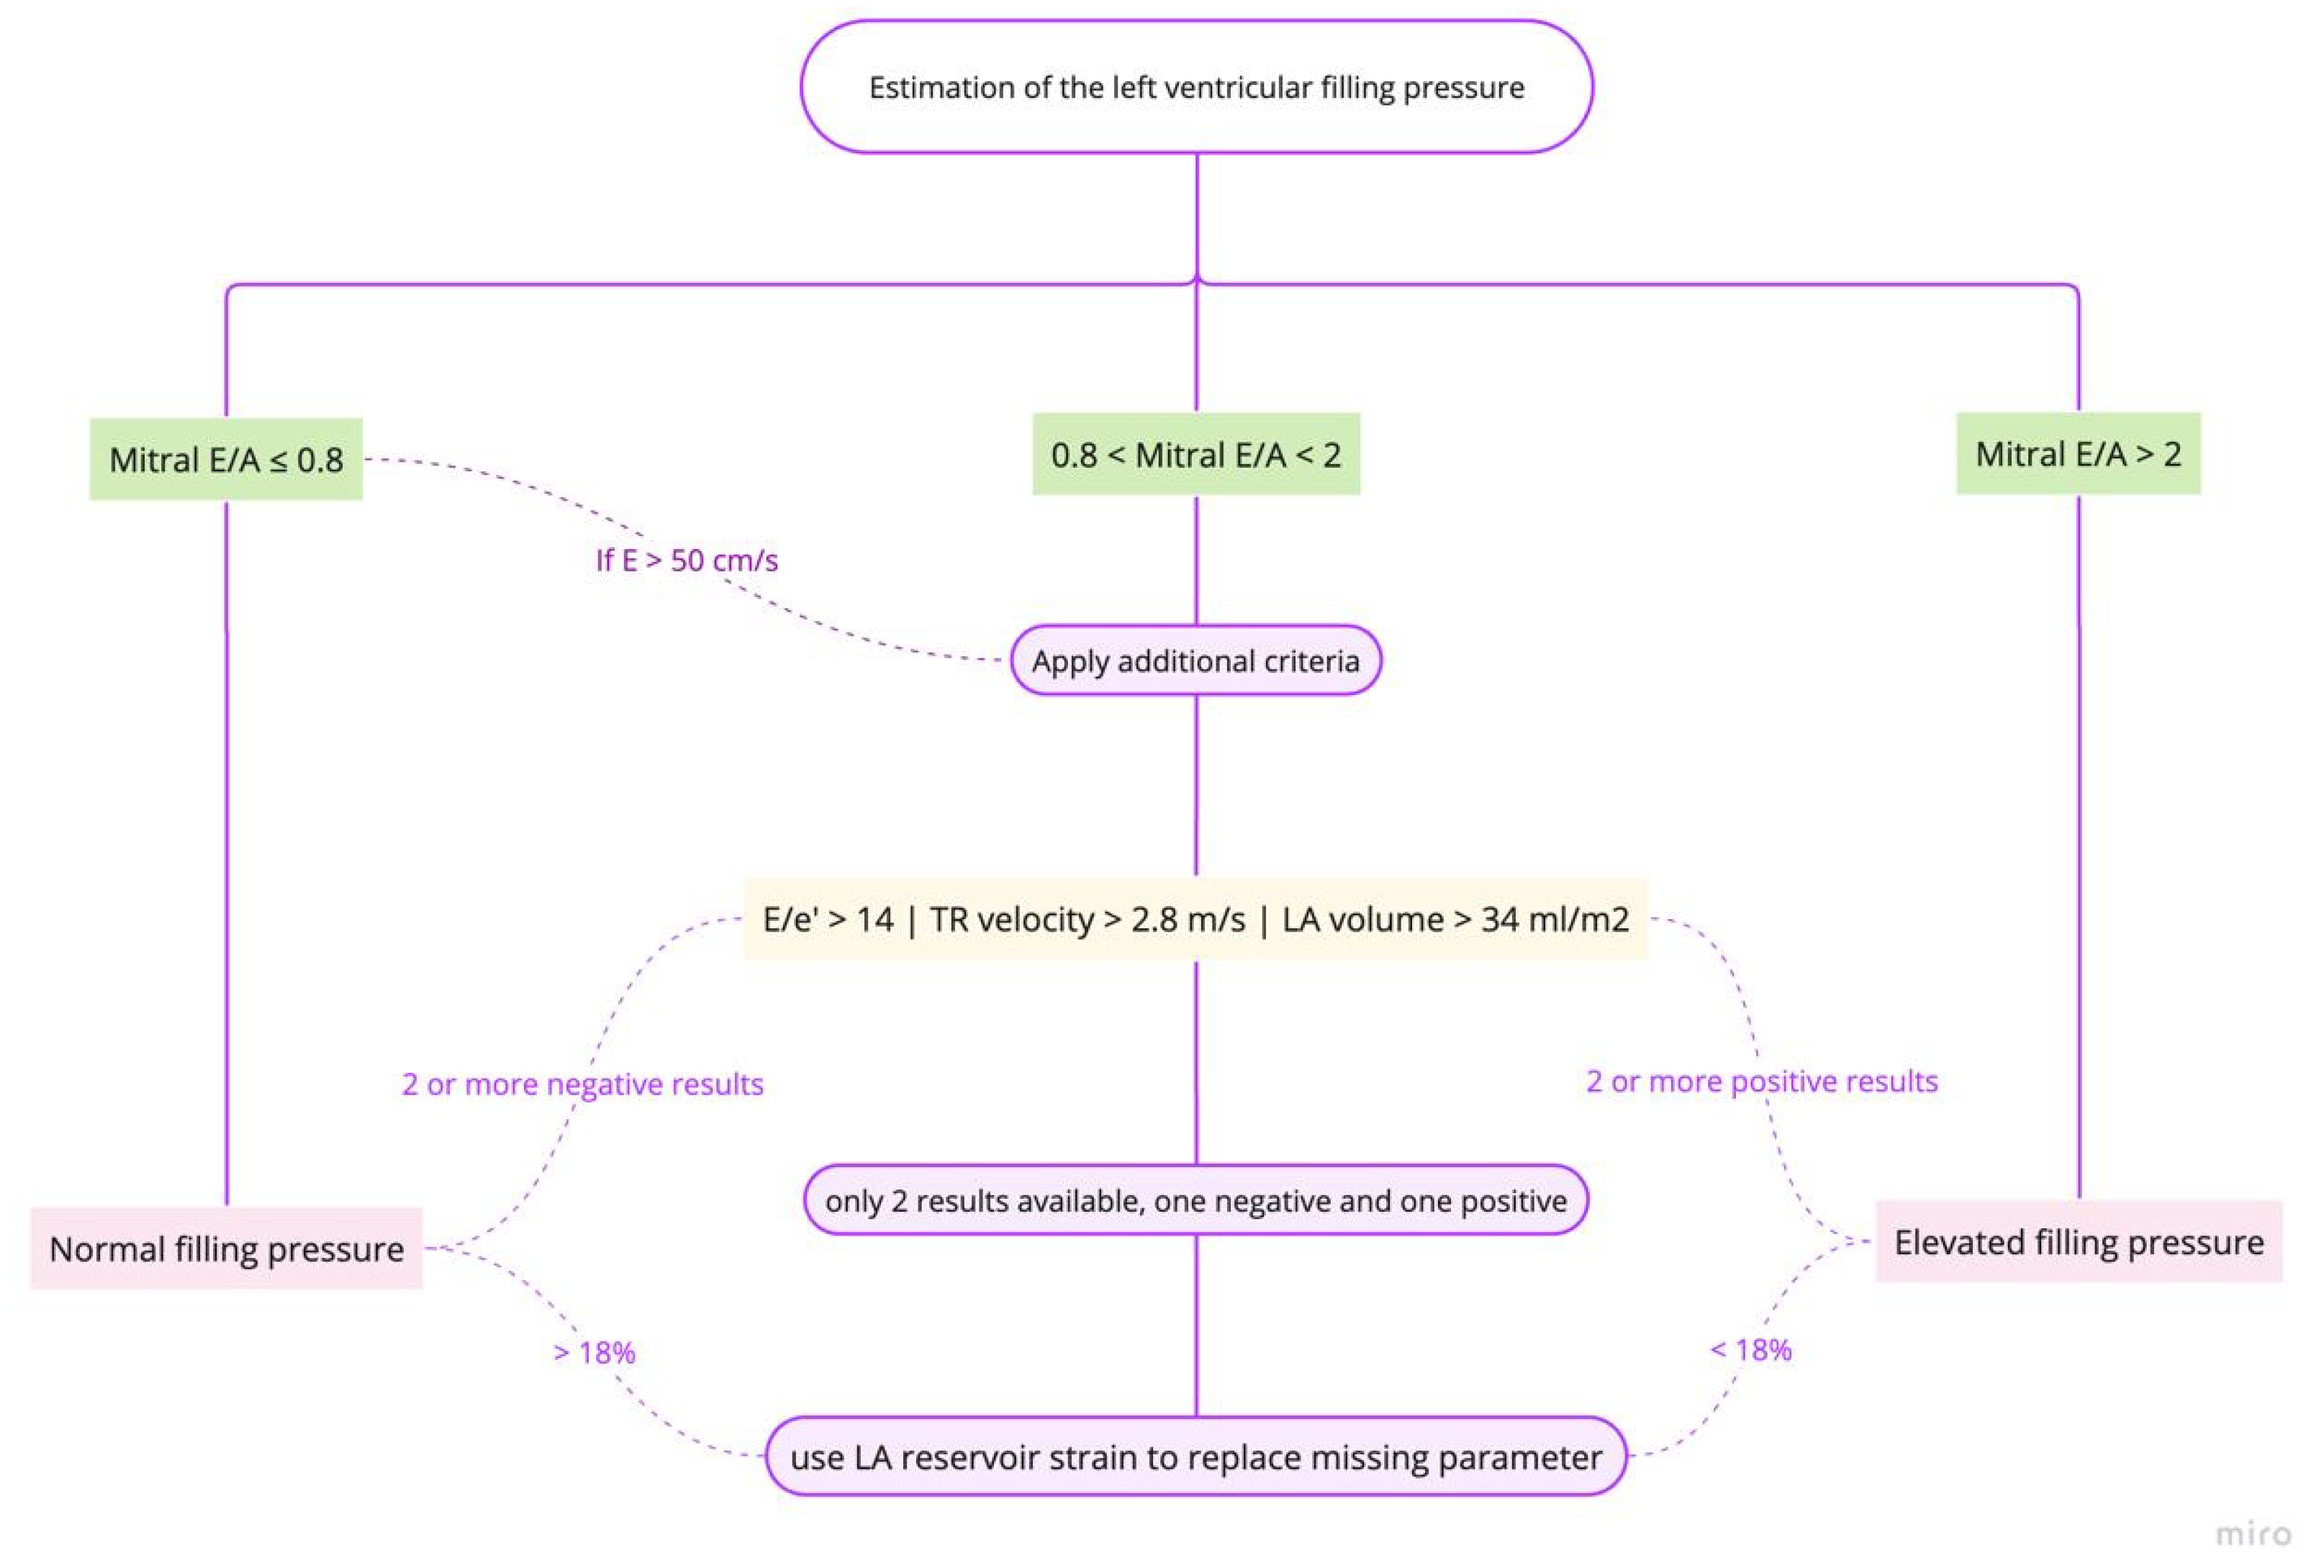

- Estimation of left ventricular (LV) filling pressures

| Echocardiography | Estimates LV filling pressures and assesses cardiac function. | Essential for managing HF; provides prognostic information. | Highly sensitive for assessing LVFP; useful in guiding therapy. | Predicts outcomes based on LVFP and cardiac function. |

- Andersen, O.S.; Smiseth, O.A.; Dokainish, H.; Abudiab, M.M.; Schutt, R.C.; Kumar, A.; Sato, K.; Harb, S.; Gude, E.; Remme, E.W.; et al. Estimating Left Ventricular Filling Pressure by Echocardiography. J. Am. Coll. Cardiol. 2017, 69, 1937–1948. [Google Scholar] [CrossRef] [PubMed]

- Smiseth, O.A.; Morris, D.A.; Cardim, N.; Cikes, M.; Delgado, V.; Donal, E.; Flachskampf, F.A.; Galderisi, M.; Gerber, B.L.; Gimelli, A.; et al. Multimodality imaging in patients with heart failure and preserved ejection fraction: An expert consensus document of the European Association of Cardiovascular Imaging. Eur. Heart J.-Cardiovasc. Imaging 2022, 23, e34–e61. [Google Scholar] [CrossRef] [PubMed]

- Lancellotti, P.; Galderisi, M.; Edvardsen, T.; Donal, E.; Goliasch, G.; Cardim, N.; Magne, J.; Laginha, S.; Hagendorff, A.; Haland, T.F.; et al. Echo-Doppler estimation of left ventricular filling pressure: Results of the multicentre EACVI Euro-Filling study. Eur. Heart J. Cardiovasc. Imaging 2017, 18, 961–968. [Google Scholar] [CrossRef]

- Cameli, M.; Lisi, M.; Mondillo, S.; Padeletti, M.; Ballo, P.; Tsioulpas, C.; Bernazzali, S.; Maccherini, M.; Colella, A.; Pierli, C.; et al. Left atrial longitudinal strain by speckle tracking echocardiography correlates well with left ventricular filling pressures in patients with heart failure. Cardiovasc. Ultrasound 2010, 8, 14. [Google Scholar] [CrossRef] [PubMed]